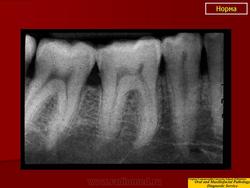

Возрастные особенности.